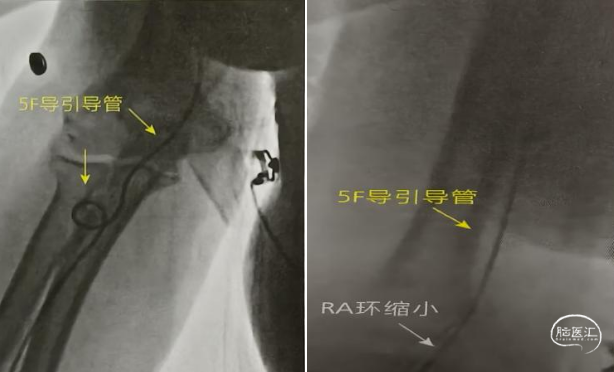

老年患者桡动脉血管在近肘部常常形成环状迂曲,导丝、导管难以通过,这种情况下将泥鳅导丝尝试通过到达上臂,往往能够拉直血管,在通过泥鳅导丝顺利输送导管。部分患者泥鳅导丝不能前行到达上臂,需要助手或护士将双手置于迂曲部位远段和近段,双手对拉绷紧肌肉,常常“哗啦一下”血管伸直。如上图。